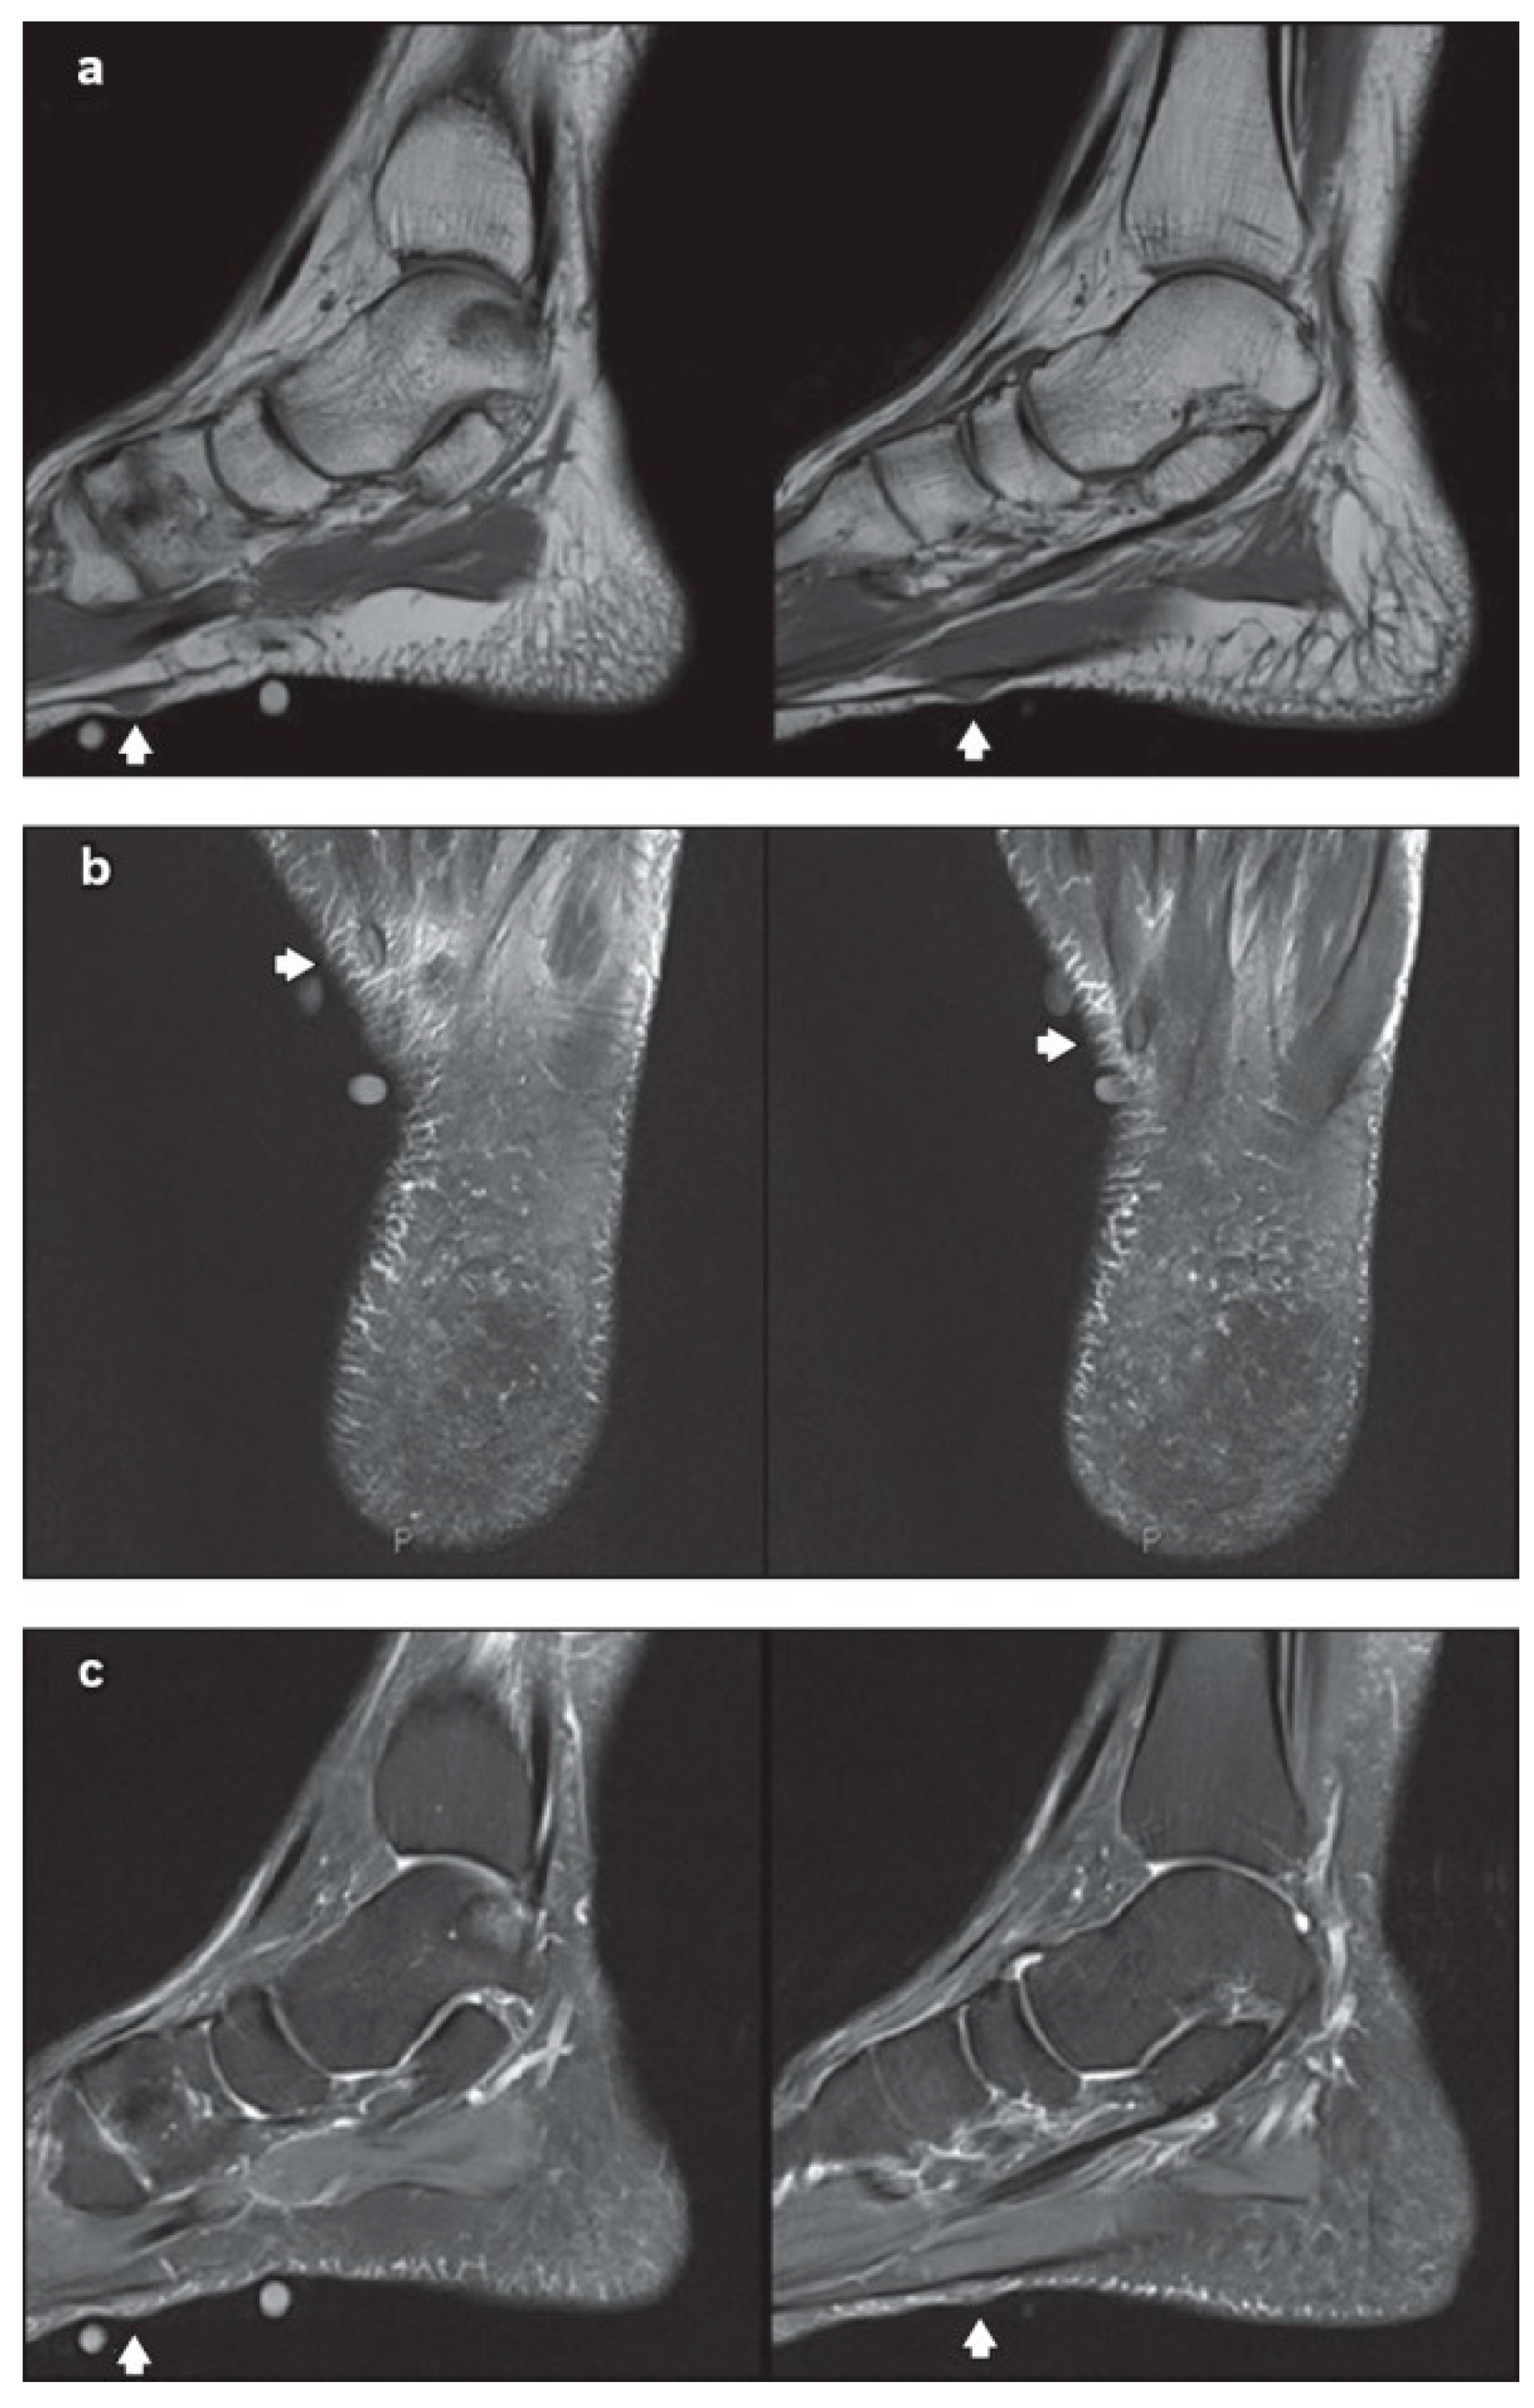

5.1. Imaging